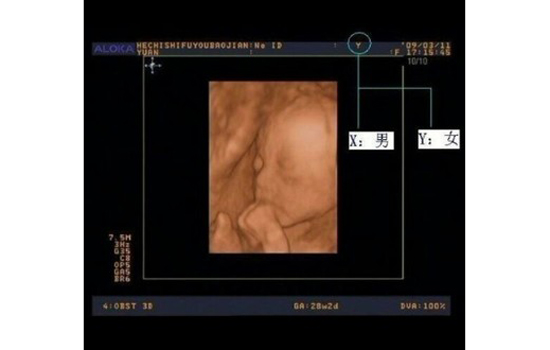

三、看b超单

孕妇在中晚期做B超时,可留心任意一张B超单(早孕的不能显示的),看看B超图像上最顶是不是有一橫行,橫行中间会有显示Y或X的字母,如果是Y就代表你怀的是女孩,X就是男孩。不过有的地方很严格,B超单上可能没有。

另外,还可看B超单上医生所写的“*”号两侧数字相除的值超过2几乎可以确定是男的,1.5左右是个临界值,不太好判断。